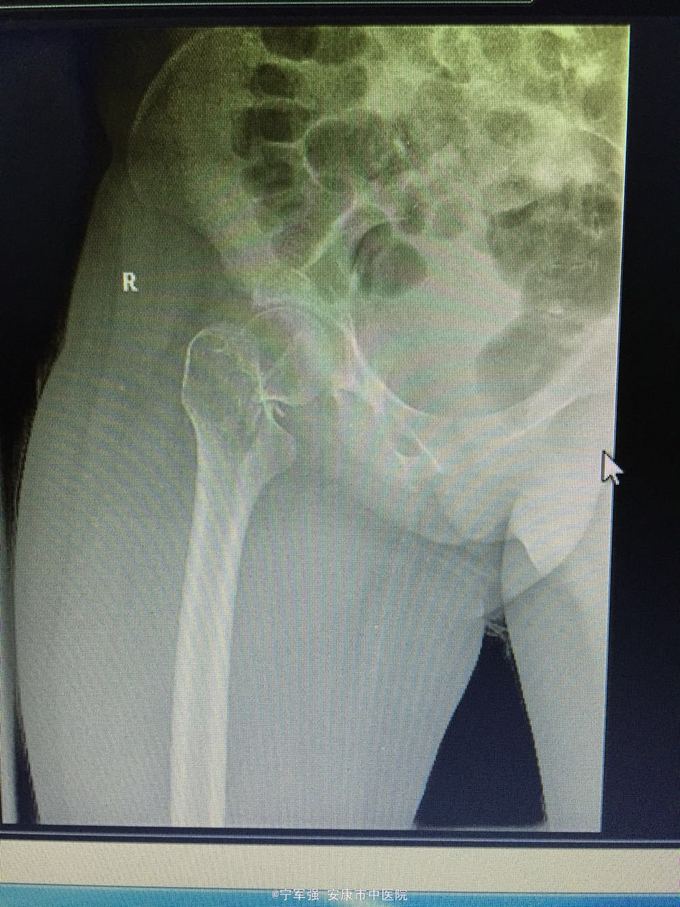

女性,20岁,外伤后右髋部疼痛不适活动受限 伤前身体尚可,5个月前有右大腿不适感,当时未行X线检查

查体:右髋部稍肿,局部压痛(+),纵向叩击痛阳性,右下肢短缩约1.5CM,末梢血运及皮肤感觉良好。 肿瘤标志物(-),碱性磷酸酶不高。

右股骨颈病理性骨折 处理:1.进一步完善检查髋关节MRI。 2.病检,确定性质; 3.消肿对症治疗; 4.择期植骨内固定术